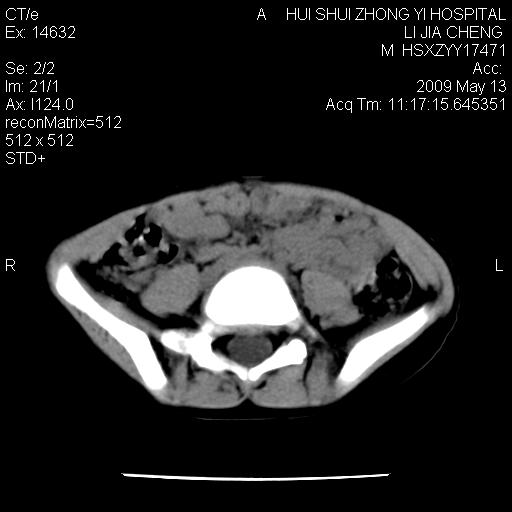

标题: PED1887:男性,6岁。反复脐周疼痛2年余。请各位老师看下腹 [打印本页]

标题: PED1887:男性,6岁。反复脐周疼痛2年余。请各位老师看下腹

该患者可自行好转,大小便未见异常,化验:便未见虫卵,血常规:wbc:8000;淋巴3600,中性45%

肠道准备不足,im15---------------------18左侧腹腔病变?

来源于十二指肠水平部病变?建议行进一步检查。

肠管管壁均匀增厚,炎性可能

考虑腹疝可能。

是小肠,壁稍厚可能是肠腔未很好充盈所致,腹部ct扫描未见明显异常。